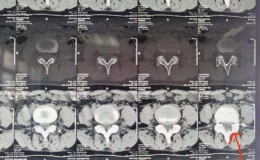

患者李某某,男,59岁,系“摔伤致腰背部疼痛伴活动受限2小时余”入院;入院后予以完善相关检查,CT示:腰2椎体爆裂性骨折,侵占部分椎管,L2左侧横突骨折。MRI提示:L2椎体压缩性骨折,L2右侧椎板骨折;腰椎退行性变;L2/3、L5/S1椎间盘突出。摄片提示:L2椎体楔形改变,椎体前缘压缩1/3。

骨伤一科陈孝贵主任指出:根据患者病史、体征及影像学表现,患者腰椎压缩性骨折(L2 爆裂性)诊断明确,对于脊柱骨折保守治疗患者,需要长期卧床,极易出现褥疮、坠积性肺炎、下肢静脉血栓形成、肺栓赛等并发症,保守治疗椎高丢失会引起腰椎后凸畸形、慢性腰疼及继发腰椎不稳等后遗症,对于该患者,手术指针明确,手术目的:恢复椎高及清理椎管占位,促进早期下地,减少并发症及远期后遗症。建议患者行微创手术治疗方案-经皮椎弓根螺钉复位内固定术,患者及其家属同意并积极配合治疗方案,积极术前准备,在排除手术禁忌后,陈主任为其行手术治疗,手术顺利,术后2天即可佩戴支具下床活动。